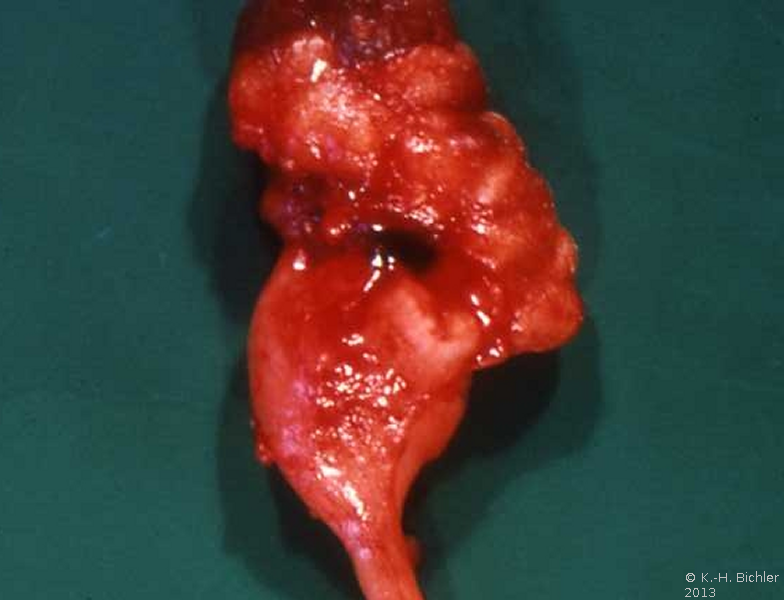

Die Nieren sind klein und haben ein Gewicht von ca. 40g. Die Nierenoberfläche ist diffus-höckrig. Refluxnarben finden sich an den Polen und der Mitte des Organs. Auf der Schnittfläche zeigt sich das Parenchym reduziert, z.T. mit abgeflachten Papillen und Bildung von Exkavationen bzw. Rezessi (Abbildung 7,8,9)

Beispiele Nieren mit ausgeprägter Refluxnephropathie.

Computertomographie zur Diagnostik der kleinen Niere. Zum Beispiel eine pyelonephritisch veränderte linke Niere im Computertomogramm und im weiteren Beispiel CT und Organpräparat einer rechtsseitigen kleinen Niere.

Und in einem weiteren Beispiel CT und Organpräparat einer rechtseitigen "kleinen Niere" (Abbildung 11, 12ab).